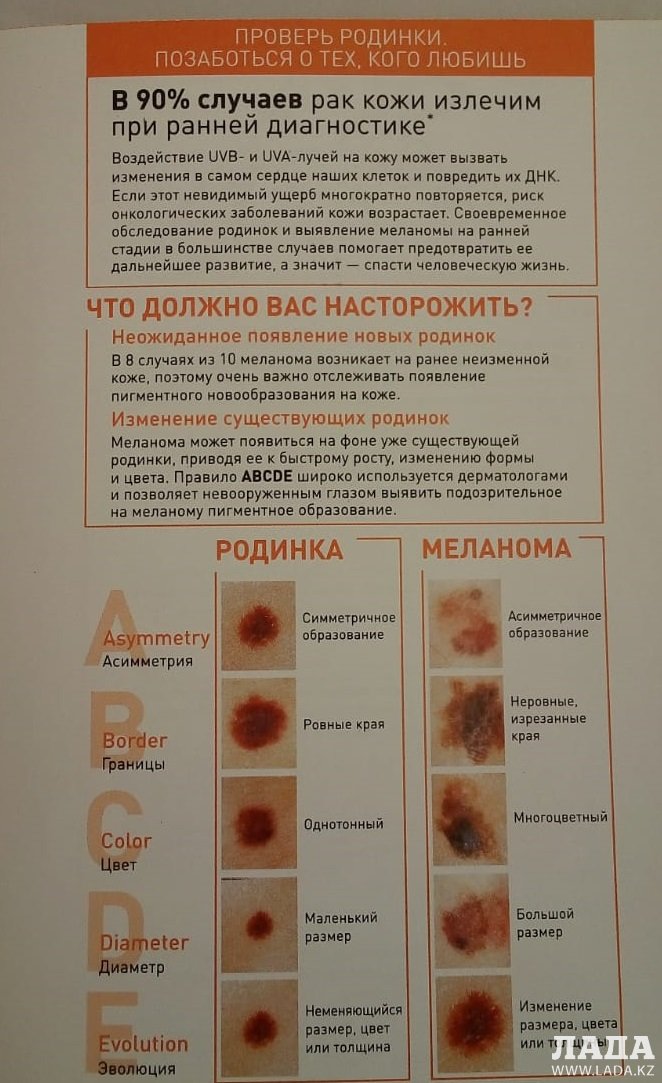

Бесплатное обследование на онкологию: информация и ресурсы